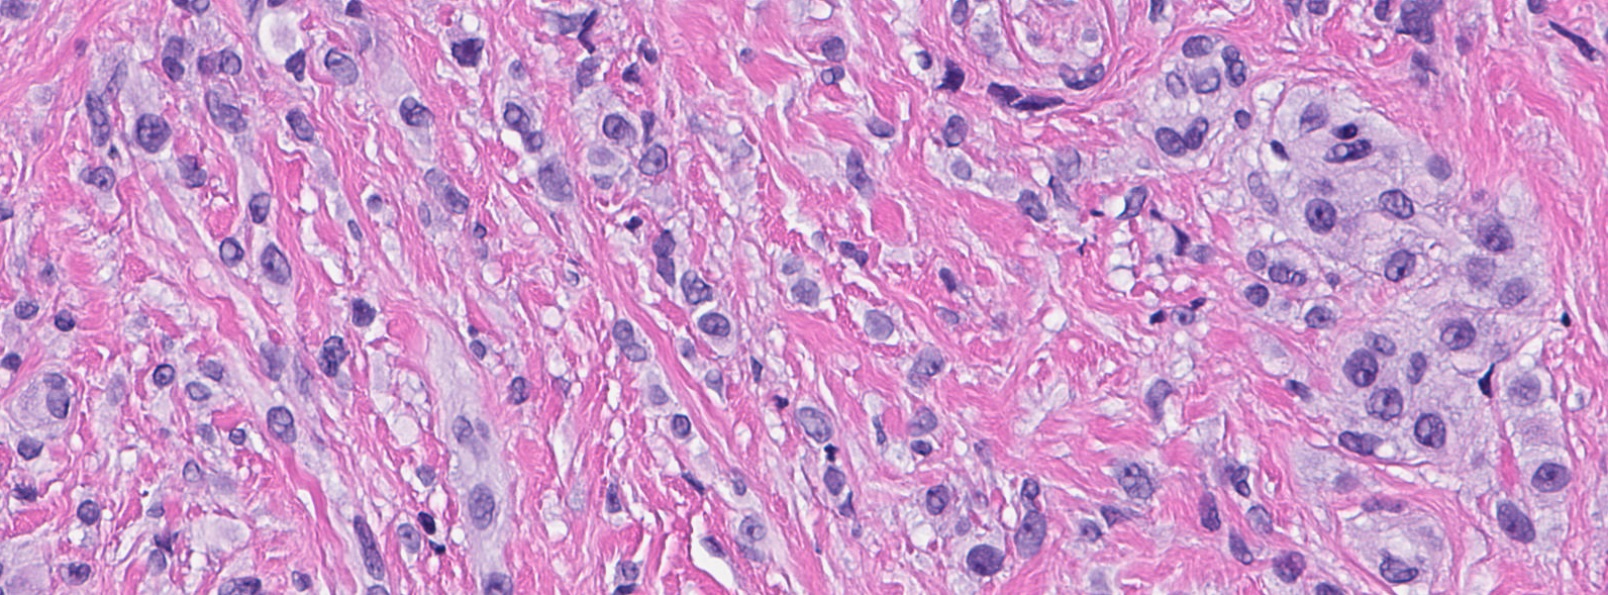

Microscopic (histologic) images

- Bland, uniform, short to elongated spindle cells arranged as short haphazard intersecting fascicles admixed with bands of hyalinized, brightly eosinophilic collagen and variable amounts of fat

- No more than mild nuclear atypia

- Mitoses usually absent, atypical mitoses and necrosis absent

- Mast cells common, perivascular lymphocytic infiltrates on occasion

- Cellular: dense proliferation of myofibroblasts, ratio of spindle cells to collagen increased compared with classical variant, may have infiltrative borders, storiform or herringbone arrangement

- Epithelioid: oval to polygonal cells arranged in clusters, cords, alveolar groups, linear strands, mono, bi or multinucleated, may have eccentrically placed nuclei with small nucleoli, well defined cell borders, single file arrangement may mimic invasive lobular carcinoma (Am J Surg Pathol 2009;33:1085)